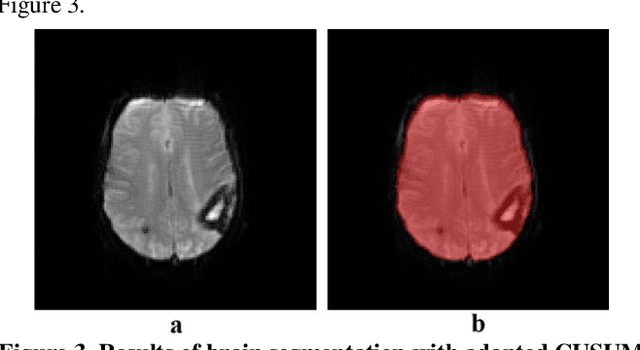

Abstract:This paper presents a new approach for relatively accurate brain region of interest (ROI) detection from dynamic susceptibility contrast (DSC) perfusion magnetic resonance (MR) images of a human head with abnormal brain anatomy. Such images produce problems for automatic brain segmentation algorithms, and as a result, poor perfusion ROI detection affects both quantitative measurements and visual assessment of perfusion data. In the proposed approach image segmentation is based on CUSUM filter usage that was adapted to be applicable to process DSC perfusion MR images. The result of segmentation is a binary mask of brain ROI that is generated via usage of brain boundary location. Each point of the boundary between the brain and surrounding tissues is detected as a change-point by CUSUM filter. Proposed adopted CUSUM filter operates by accumulating the deviations between the observed and expected intensities of image points at the time of moving on a trajectory. Motion trajectory is created by the iterative change of movement direction inside the background region in order to reach brain region, and vice versa after boundary crossing. Proposed segmentation approach was evaluated with Dice index comparing obtained results to the reference standard. Manually marked brain region pixels (reference standard), as well as visual inspection of detected with CUSUM filter usage brain ROI, were provided by experienced radiologists. The results showed that proposed approach is suitable to be used for brain ROI detection from DSC perfusion MR images of a human head with abnormal brain anatomy and can, therefore, be applied in the DSC perfusion data analysis.